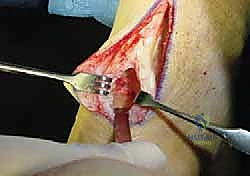

2. الشق الجراحي الدقيق (Incision)

يقوم الدكتور هطيف بعمل شق جراحي طولي دقيق في الجزء الخلفي من الكاحل. بفضل خبرته في الجراحة الميكروسكوبية، يتم التعامل مع الأنسجة المحيطة بحذر شديد للحفاظ على الأعصاب والأوعية الدموية.

4. عزل وحصاد وتر FHL (Tendon Harvesting)

يتم تحديد مسار وتر FHL الذي يقع أعمق قليلاً من وتر أخيل. يتم فصل الوتر بعناية من نقطة اتصاله السفلية (عند منتصف القدم تقريباً) لضمان الحصول على طول كافٍ للنقل. وتجدر الإشارة هنا إلى أن قطع هذا الوتر لا يؤثر بشكل ملحوظ على وظيفة المشي أو حركة إصبع القدم الكبير، حيث تتولى عضلات أخرى هذه المهمة بكفاءة.

5. نقل وتثبيت الوتر (Tenodesis & Fixation)

هنا يتجلى الفن الجراحي. يتم حفر نفق صغير جداً في عظم الكعب (Calcaneus). يُسحب وتر FHL القوي ويُزرع داخل هذا النفق العظمي. يتم تثبيته باستخدام مسمار تداخلي حيوي (Bio-interference screw) يندمج مع العظم بمرور الوقت، مما يوفر تثبيتاً صخرياً قوياً.

بالإضافة إلى ذلك، يقوم الدكتور هطيف بخياطة ما تبقى من وتر FHL مع وتر أخيل الأصلي (Side-to-side anastomosis) لتعزيز القوة الميكانيكية المزدوجة.